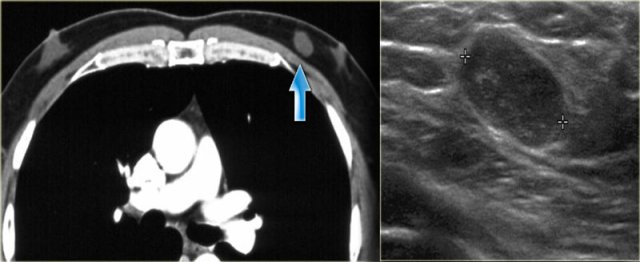

Gynecomastia nodular pattern: Incidental finding on CT-scan Gynecomastia nodular pattern: Incidental finding on CT-scan

On the left unilateral gynecomastia.

This was an incidental finding on a CT-scan done for some other reason.

By definition gynecomastia is 2 cm or more of subareolar tissue in a non obese male.

It is a common 'normal' finding, that is seen in 55% of men at autopsy.

The peak incidence is 60 - 69 years.

It is significant if it is new or symptomatic.

In elderly males gynecomastia makes up 65% of all breast lesions.

25% is carcinoma and 10% are other lesions.

Mammogran and rotated ultrasound image Mammogran and rotated ultrasound image

On the left a mammogram and an ultrasound image of a patient with a nodular glandular pattern of gynecomastia.

Notice that it is situated underneath the nipple.

The ultrasound image shows the typical appearance of gynecomastia: a hypoechoic mass with lobulation or even spiculation.

If this was seen in a woman, you would say that this is a mass with microlobulation and spiculation, i.e. Birads IV or V.

In a man this is typical for gynecomastia.

On the left the same ultrasound image, but now in the normal position.

Notice how 'malignant' it looks.